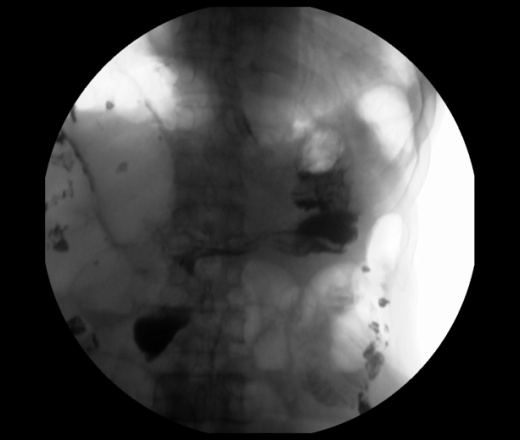

Мужчина 73 года. Жалобы на сниженный аппетит, слабость. Исследование выполенено через несколько дней после ирригоскопии. По результатам ЭФГДС гастрит.

Угол желудка развернут, ригиден. Стойкое циркулярное сужение антрального отдела.Перистальтики нет. Складки прослеживаются.

Эндофитный C-r антрального отдела.